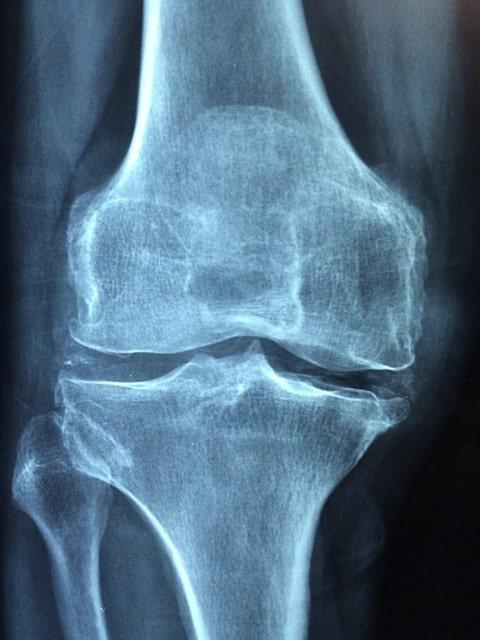

Der Welt-Rheuma-Tag wird jährlich am 12. Oktober begangen, um das Bewusstsein für rheumatische Erkrankungen zu erhöhen und auf die Bedeutung einer rechtzeitigen Diagnose und Behandlung hinzuweisen. Rheumatische Erkrankungen können alle Altersgruppen betreffen und zu erheblichen gesundheitlichen Einschränkungen führen.

- Eine Zusammenfassung der verschiedenen Arten von Rheuma und ihrer Symptome, sowie wie sie behandelt werden können.